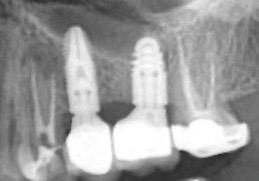

directamente a cabeza de implante para realizar una prótesis dentoalveolar de cerámica de 3 piezas, que equilibraran la oclusión y dieran soporte al labio y la mejilla (Figuras 14-17)

Figura 14. Imagen intraoral frontal postoperatoria al año de la reconstrucción.

Figura 15. Detalle de prótesis dentoalveolar cerámica en visión lateral.

Figura 16. Ortopantomografía postoperatoria.

Figura 17. Resultado final.